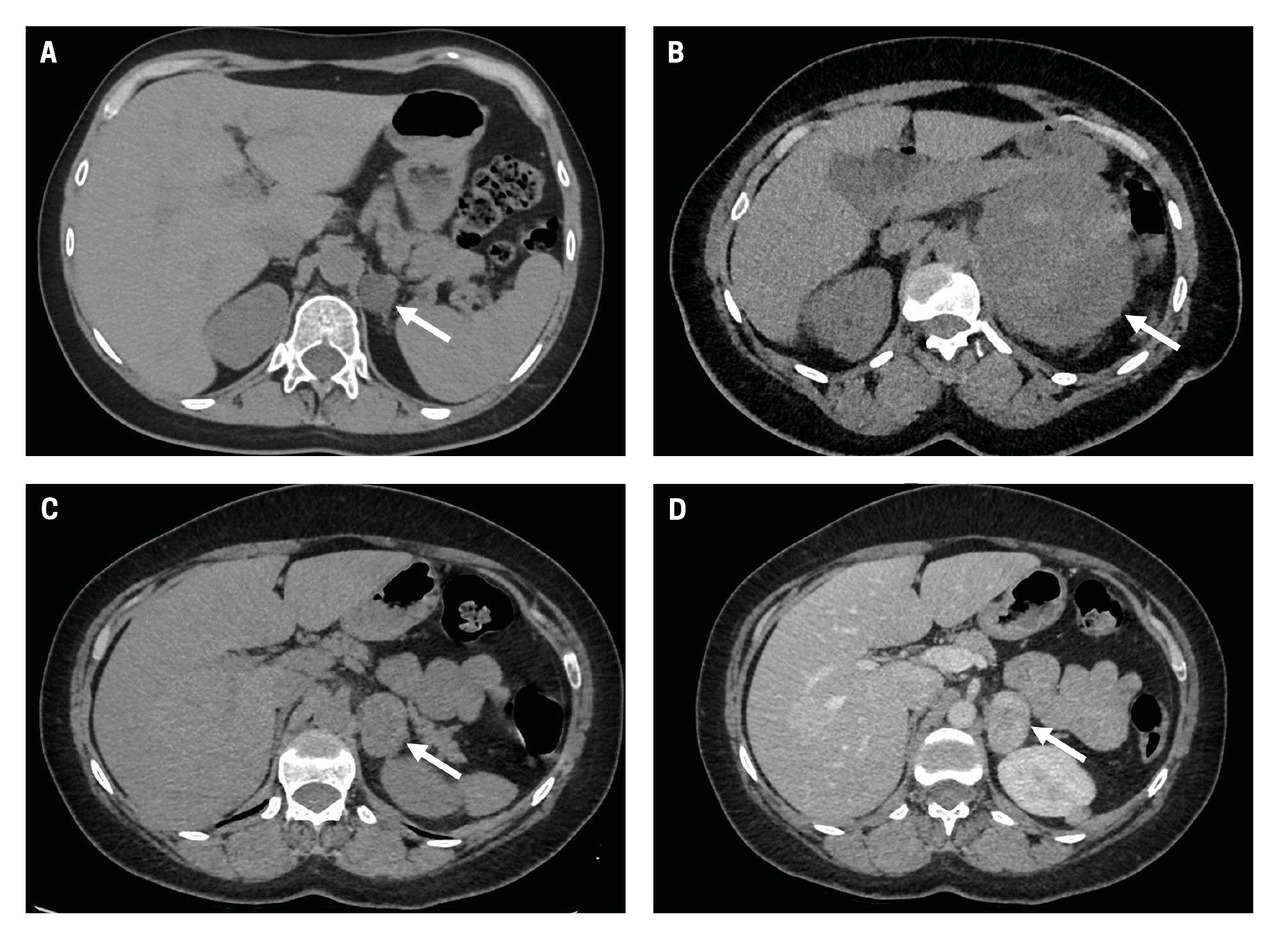

C. et D. Phéochromocytome gauche (flèches) : TDM en contraste spontané montrant une lésion à contours réguliers, légèrement hétérogène (C) et TDM avec injection de produit de contraste iodé en phase artérielle (D) montrant un rehaussement de la lésion de façon hétérogène à la suite de l’injection.